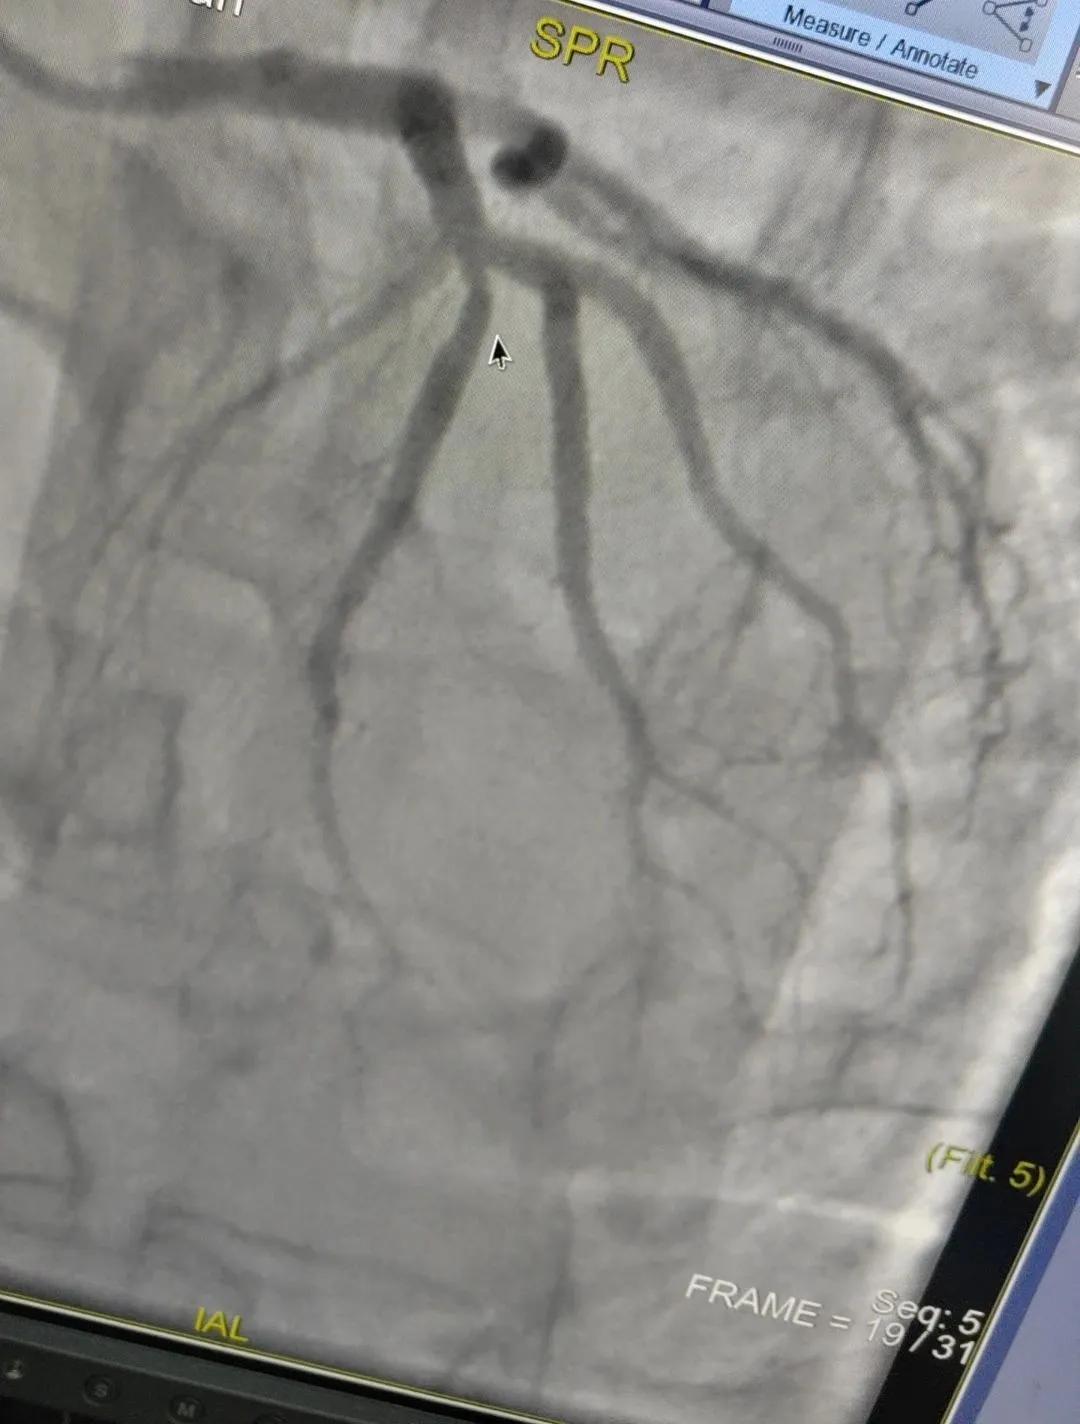

近日,漯河市中醫(yī)院成功開展了一例心腦血管聯(lián)合造影的手術(shù)。

患者男,37歲,兩周前無明顯誘因突發(fā)頭昏,伴右側(cè)肢體無力來院就診,經(jīng)過對患者病情的評估以及心內(nèi)科和腦病科醫(yī)生聯(lián)合會診,需對患者進行心腦血管聯(lián)合造影手術(shù)。由神經(jīng)內(nèi)科楊慶堂副主任與心血管內(nèi)科陳云副主任帶領(lǐng)各自的介入團隊為該患者順利進行了全腦血管造影術(shù)+心血管造影的介入檢查。

術(shù)中心血管造影顯示:LAD中段發(fā)出D1處可見約50%節(jié)段性狹窄,RCA中段狹窄約40%,PLA可見約70%狹窄病變。

腦血管造影顯示:左側(cè)頸內(nèi)動脈嚴(yán)重遷曲,左側(cè)大腦前動脈未顯影,左側(cè)大腦中動脈M1中段以遠(yuǎn)未顯影,M1近段串珠樣嚴(yán)重狹窄,顱底可見少量煙霧血管,后交通動脈未開放;右側(cè)頸內(nèi)動脈嚴(yán)重遷曲。右側(cè)大腦前動脈A1段嚴(yán)重遷曲。

心腦聯(lián)合造影不僅明確患者的病因和病變血管,還為下一步治療提供了有力的依據(jù)。